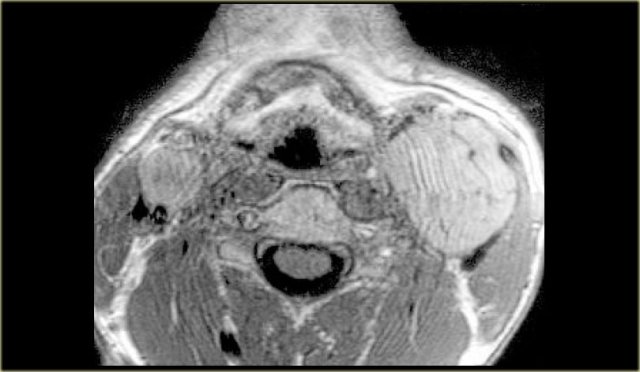

On the left a patient with bilateral swelling in the neck.

CT image at the level of the hyoid bone shows multiple rounded lesions medial to the sternocleidomastoid muscles and dorsal to the internal jugular veins.

These bilateral multiple lesions are located in the posterior cervical space.

Step 2

Analysis of the normal anatomical components of the posterior cervical space:

- Fat

The fat looks normal. - Accessory nerve

Accessory nerve pathology is expected to be unilateral. - Brachial plexus

Brachial plexus pathology like neurofibromatosis could be considered.

However we would expect continuous lesions like nerves and not these separate rounded lesions. - Primitive embryonic lymph sacs:

Congenital remnants like cystic hygroma can be bilateral.

These are confluent cystic low-density lesions.

Step 3

By exclusion we can conclude that these are bilaterally enlarged lymph nodes with homogeneous enhancement.

Homogeneous enhancement is typical for lymphoma.

Central necrosis is more typical for squamous cell carcinoma metastases.

Lymph node biopsy in this patient revealed B-cell Non-Hodgkin lymphoma.